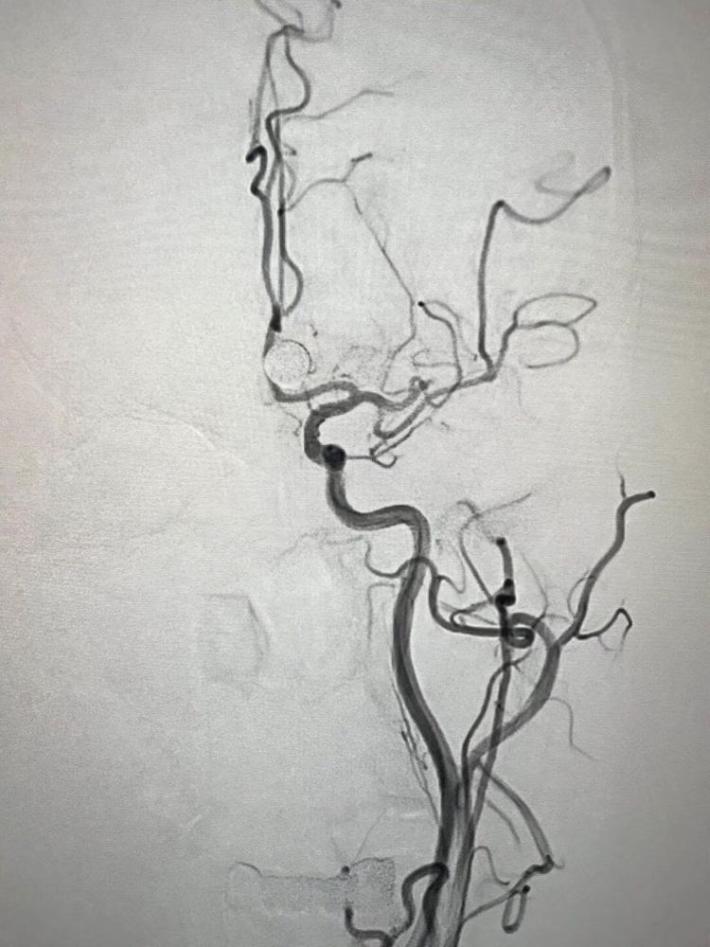

造影可见左大脑中动脉主干内血栓,下干稍远还有一块。

麻醉如履薄冰,手术也还顺利,两次取栓,一次取通大脑中动脉主干,一次取通下干。手术时间半小时。